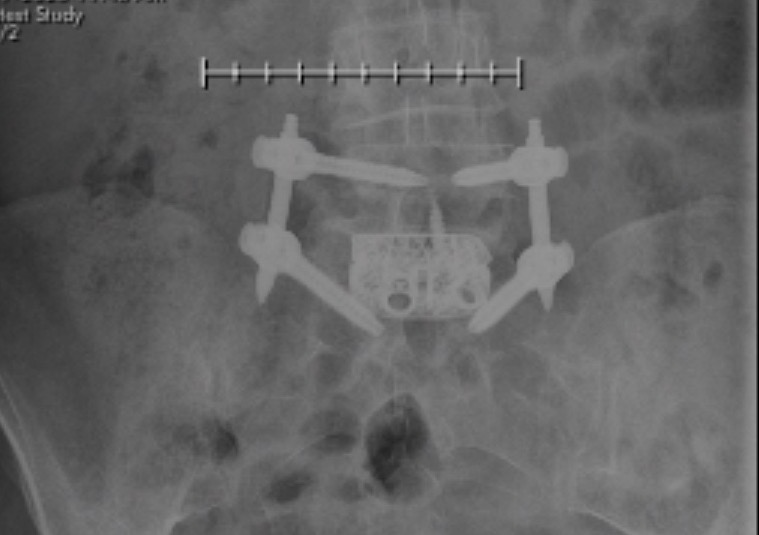

Spinal Decompression Surgery

I have always enjoyed an active lifestyle until a herniated disc caused unrelenting sciatica for almost 10 months. After meeting with less than satisfactory results with epidural injections and physical therapy, I consulted with Dr. Harvinder Sandhu in early July of 2014. I was immediately impressed with the effort Dr. Sandhu had made to fully understand my personal condition before he walked into the examination room. With great patience and demeanor, he at once made me feel confident that he was going to provide the help I needed. I felt so sure that I was in the right hands that I made arrangements for surgery as soon as possible. Less than two weeks later, I had my surgery. Every doctor, nurse, and technician I encountered was friendly, courteous and engaging. In fact, Hospital for Special Surgery runs like a well oiled machine. Dr. Sandhu and his team did a fantastic job, and when I awoke from anesthesia, I was pain free. 7 weeks after surgery, I am in physical therapy, and feeling great. Sciatica is a thing of the past, and I am looking to resuming table tennis and cycling, two of my passions in life.